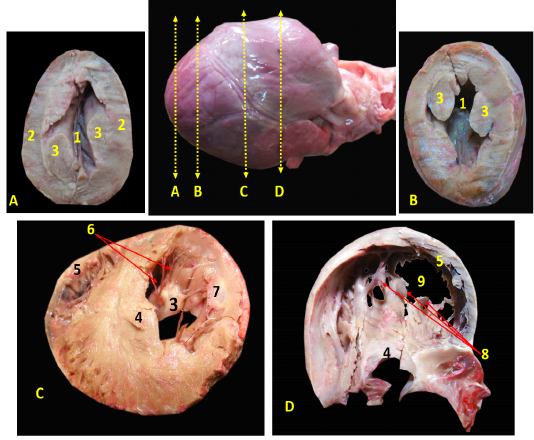

Showing the separated heart of red fox. A- showing the heart and lung separate with pericardium, B- showing the left side of the heart without pericardium, C- showing the right side of the heart without pericardium.

A, B, C showing the sagittal sections of the heart of red fox. With scale bar= 5mm, 1-Interventricular septum, 2- wall of left ventricle, 3- wall of right ventricle, 4- papillary muscle of left ventricle, 5- chorda tendineae of mitral valve, 6- valvular leaflet of mitral valve, 7- papillary muscle of right ventricle, 8- valvular leaflet of tricuspid valve, 9- right atrium, 10- pectinate muscle of right atrium, 11-left atrium, 12- trabeculae cornae

Showing the cross sections of the heart of red fox at different levels.